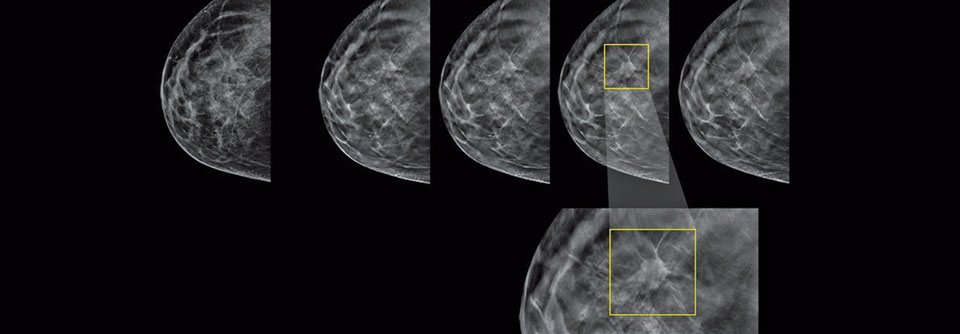

Mit einem Ultraschall zusätzlich zur Mammographie können in einer dichten Brust bis zu 45 % mehr Karzinome entdeckt werden. Es gibt daher die Überlegung, das Screening zu erweitern, erklärte Professor Dr. Werner Bader vom Klinikum Bielefeld. Internationalen Daten zufolge kann die Sonographie hier einen Vorteil bringen: In einer Metaanalyse wurde in einem Kollektiv von mehr als 80 000 Teilnehmerinnen der Zusatznutzen auf bis zu 22 neu erkannte Fälle pro 1000 Frauen beziffert.